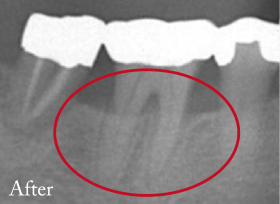

当院での治療例

-

重度歯周病

(通常は抜歯する程骨が溶けている。) -

溶けた骨が再生して

歯が保存出来た。